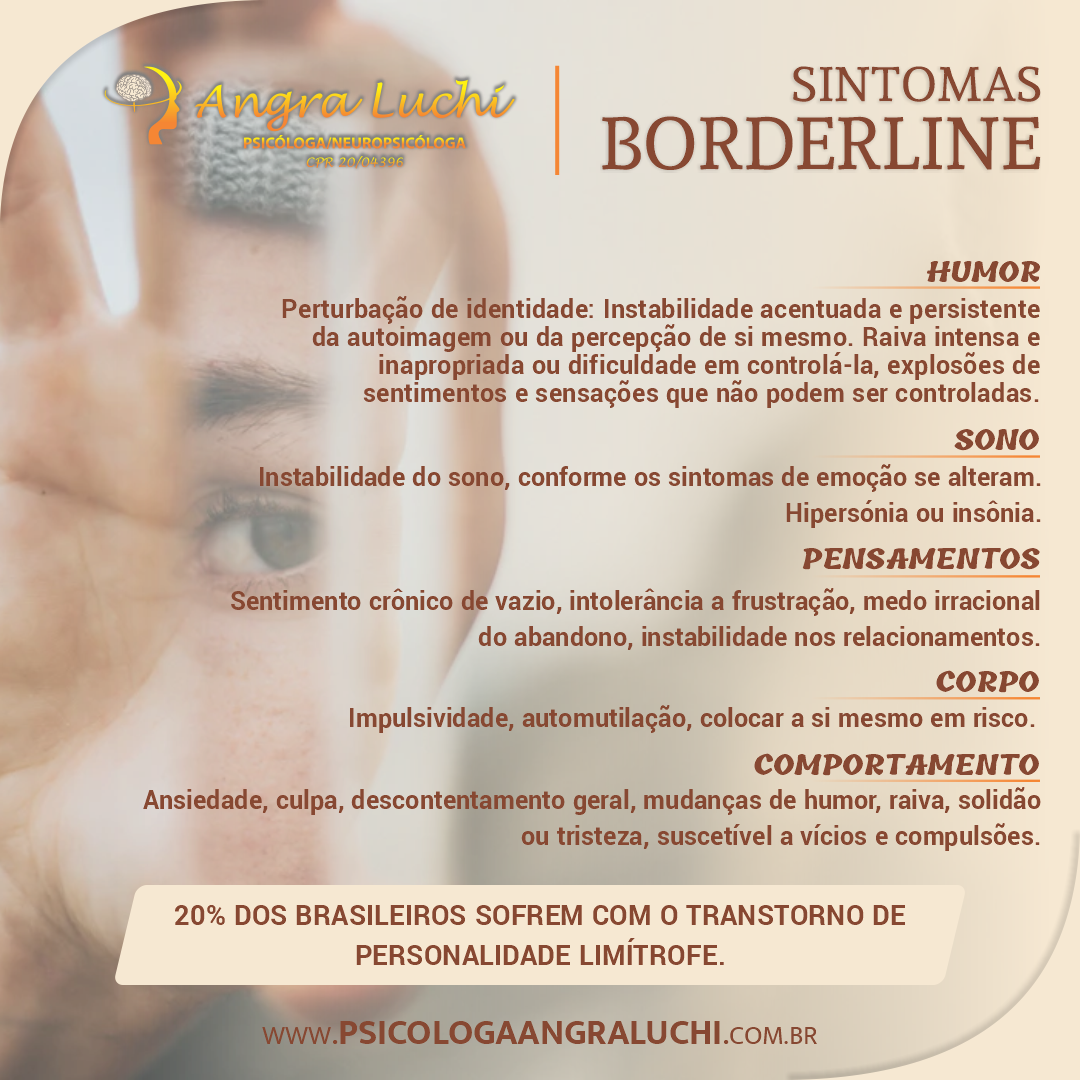

Sintomas Borderline - Psicologa Angra Luchi21 março 2025

Sintomas Borderline - Psicologa Angra Luchi21 março 2025 -